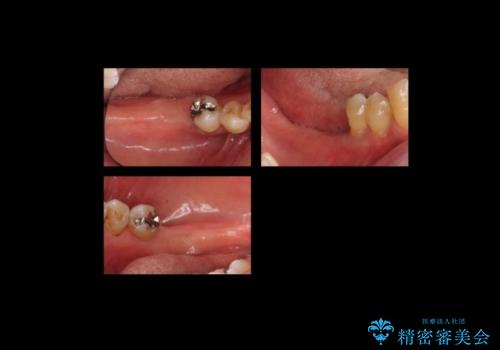

ブリッジにできない位置であったため、インプラントでかめるようにしました。

- 約250万円 右下67 インプラント2本(ストローマンインプラント20万円、カスタムアバットメント10万円、シリンダーTeC 2万円 以上2本、マイナーGBR5万円) 再根管治療 (前歯 9万円x1、小臼歯11万円x1 大臼歯:専門医による再治療 15万円x3本) ジルコニアクラウン(右上2367、右下I6I7、左上56 10万円x8 )仮歯 1万円x8本 ファイバーコア 2万円x5 セラミックインレー(左上5) 7万円x1 フラットタイプナイトガード 3万円費用は治療当時の料金となります

セラミックが欠けるのを防ぐため、また、左上7は対合歯がなく挺出してしまうのを防ぐため、ナイトガードを就寝時に装着していただいています。